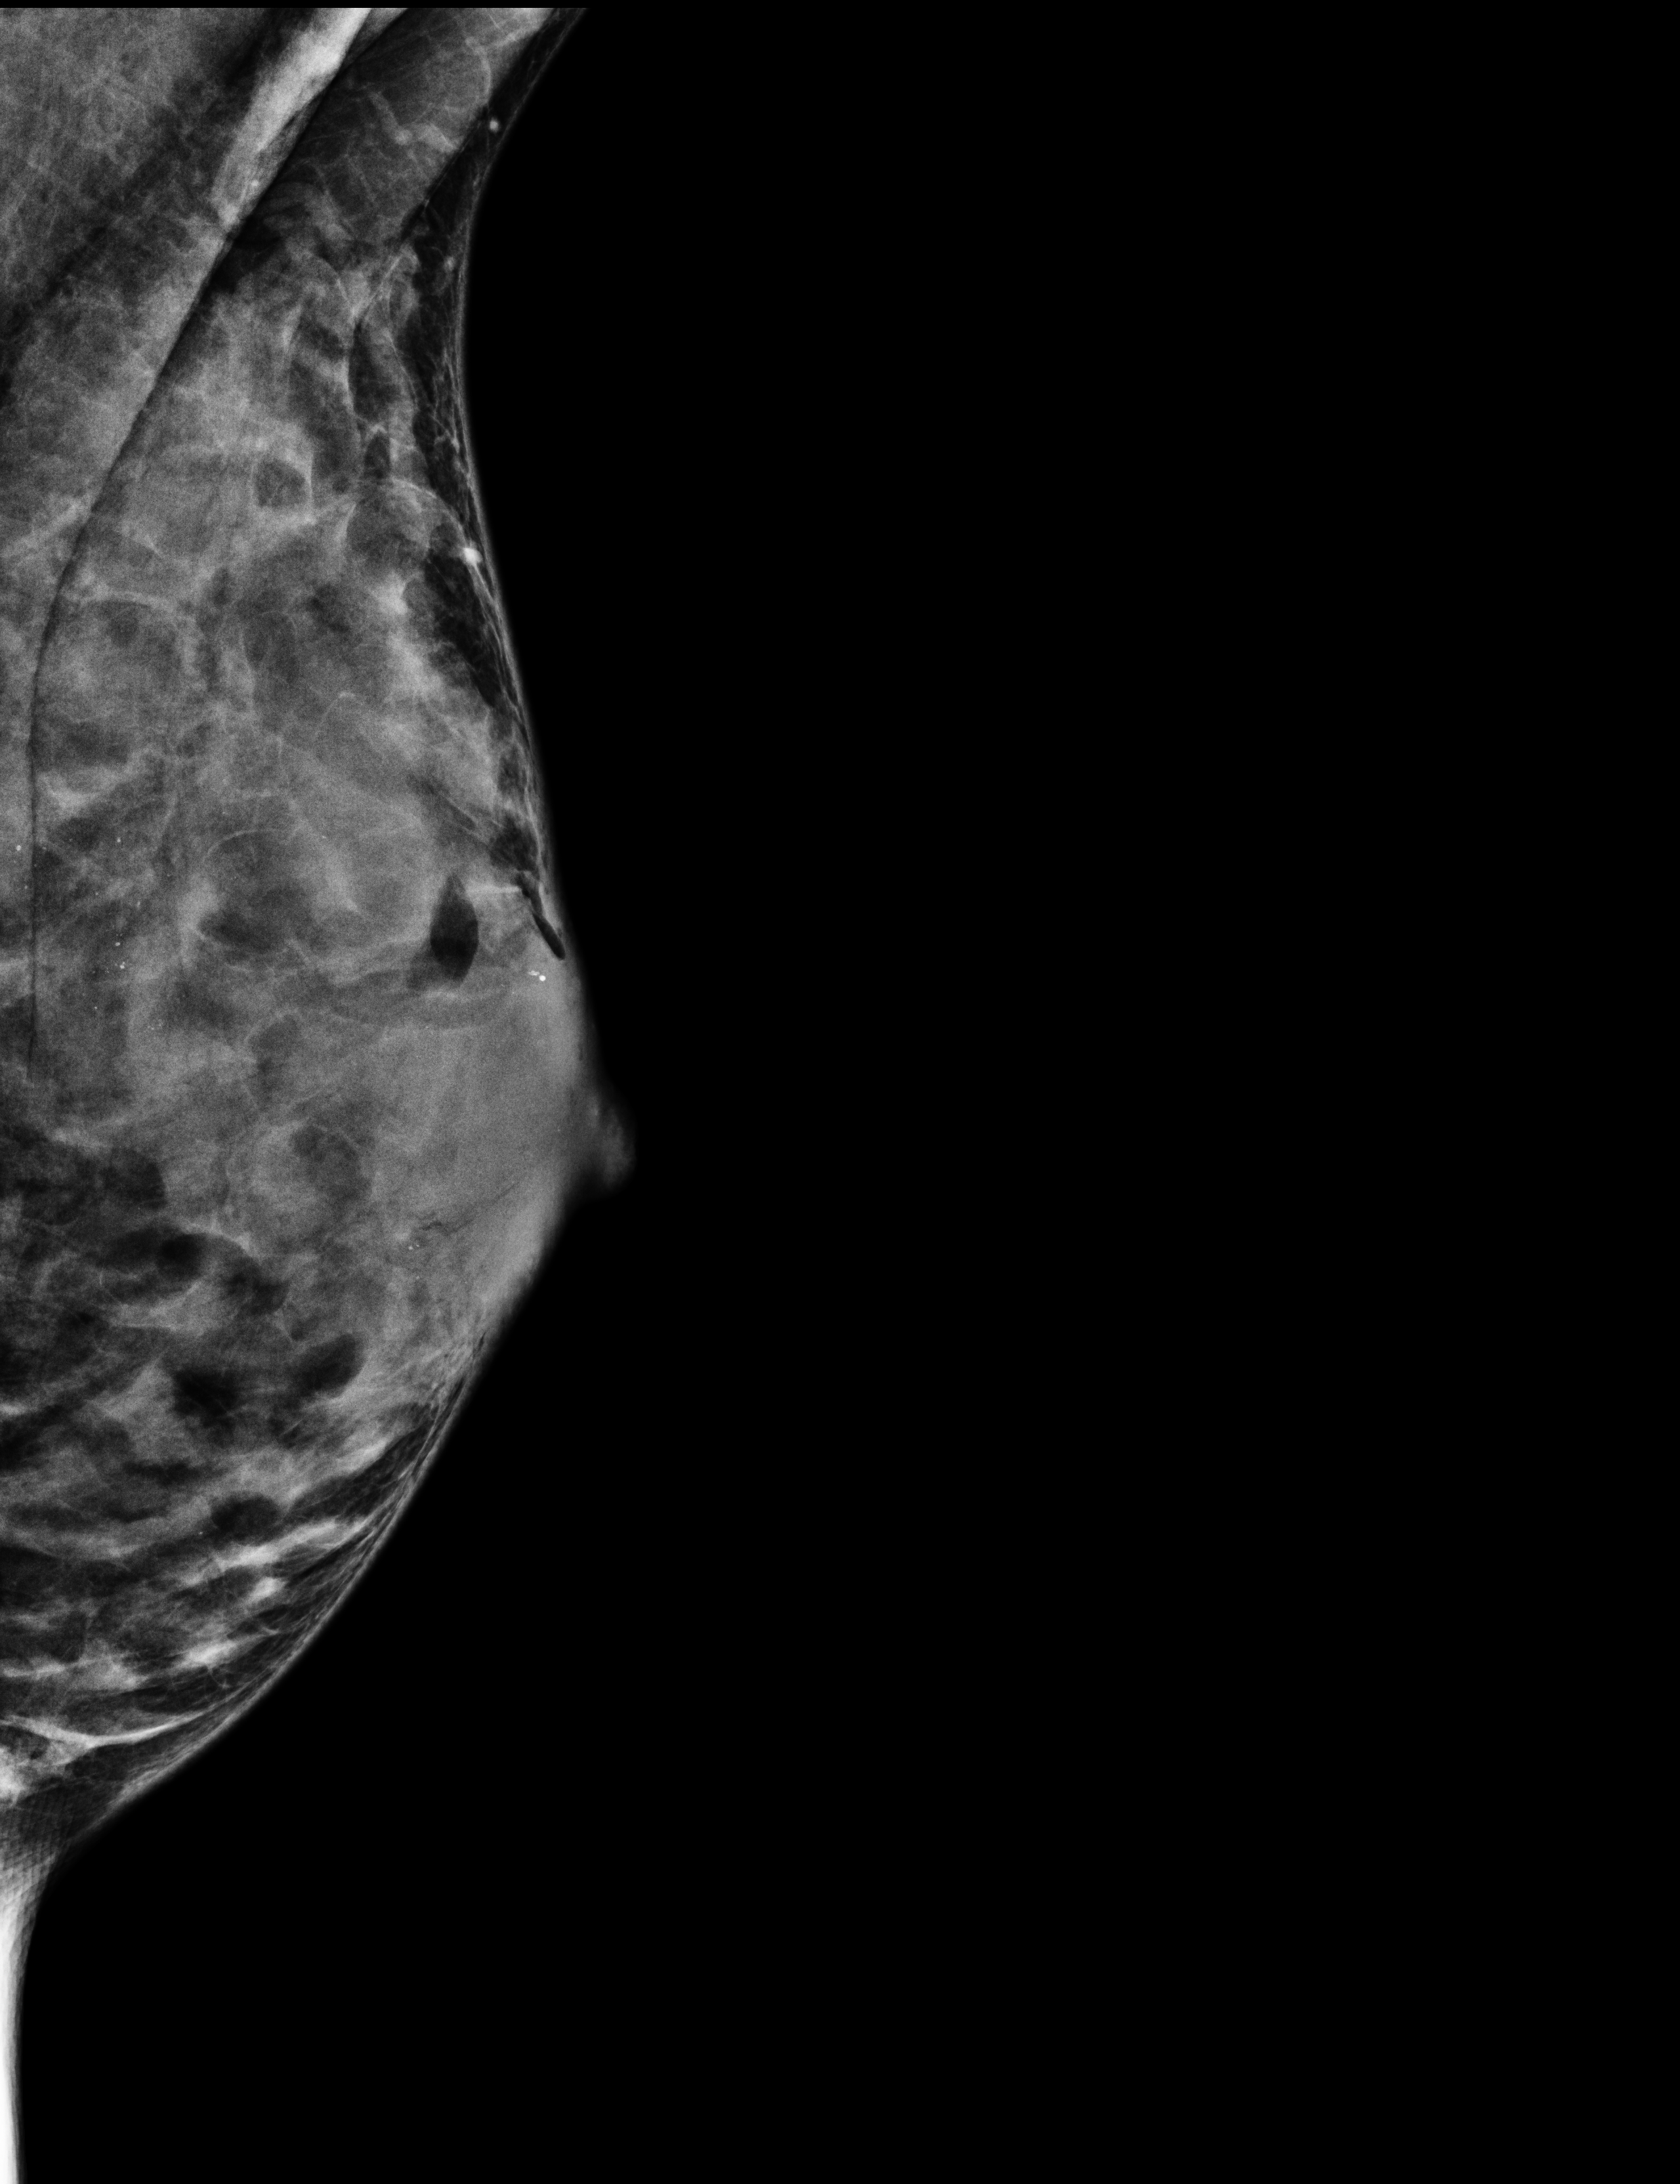

In January 2021 a check-up mammogram revealed several benign cysts in both my breasts. When I looked at the ultrasound images, I noticed how those cysts were the most prominent presence in the image; they looked like black holes in the faint, grey, oval shape of my crushed breast. At the top left-hand side of the image I read the word ‘Mamma’.

'Mastopathy with multiple smaller cysts and mastopathic microcalcifications.

No suspicious features. BI-RADS classification 2.'

• Production process

3D ultrasound pictures of breast tissue; volume of cysts traced using special software; exported as 3D model, 3D printed, sanded and polished, cast in silver.